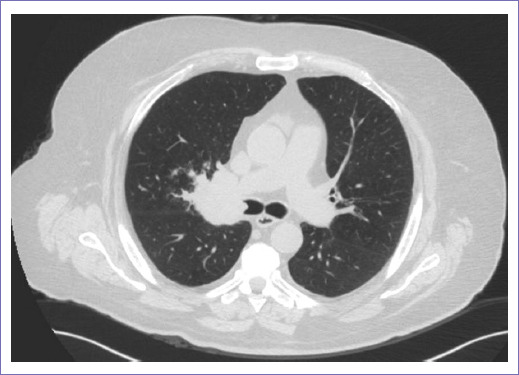

Acude al área de urgencias siete años después por hemoptisis de un mes de evolución, que inicialmente se trató en medio privado sin mejoría. Se refiere transfusión sanguínea de tres paquetes globulares con reporte de hemoglobina (Hb) externa de 8.9 postransfusión; se realizó broncoscopia en medio externo con reporte de tumor endobronquial de lóbulo superior derecho de 5 cm parahiliar y toma de biopsia con reporte histopatológico de carcinoma epidermoide, en nuestro Servicio de Urgencias con adecuada coloración mucotegumentaria y adecuado estado de hidratación, sin compromiso cardiorrespiratorio; se solicitó tomografía de tórax (Fig. 2). Laboratorios al ingreso: leucocitos 8.4, Hb 9.6, hematocrito (Hto) 29.4, recuento de plaquetas 361, creatinina 1.26, Fa 80, glucosa 99, potasio 4.0, sodio 140, tiempo de protrombina 11.8, tiempo parcial de tromboplastina 43.9 e índice internacional normalizado 1.07.

El caso se comentó en la Unidad Funcional de Tórax, donde se consideró como segundo primario pulmonar metacrónico, carcinoma epidermoide etapa clínica (EC) IIIB, central que compromete bronquio fuente derecho a menos de dos centímetros de la tráquea, sin posibilidad de control quirúrgico ni con neumonectomía.